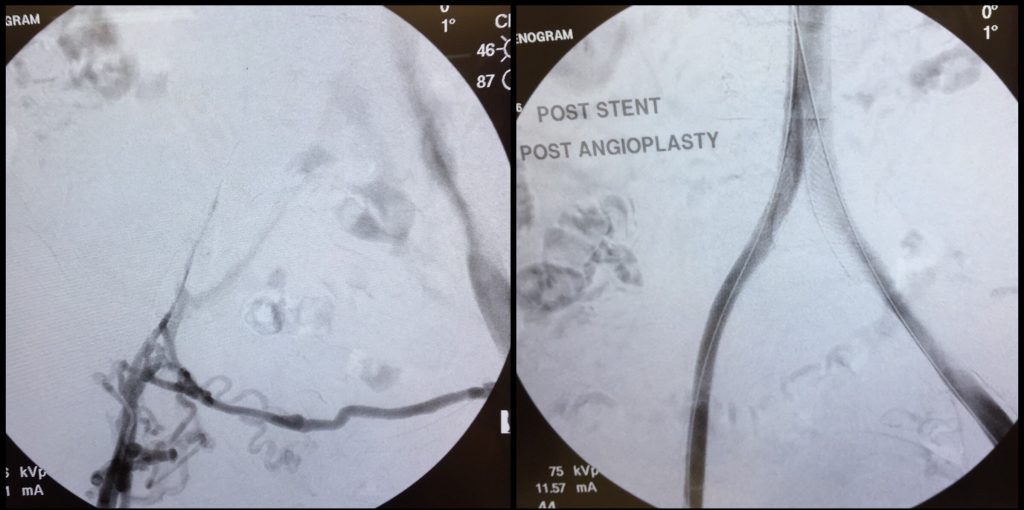

68-year-old male with bilateral lower extremity swelling and nonhealing ulcers involving both lower extremities requiring chronic wound care treatment.

The patient has a history of deep venous thrombosis and a remote history of a non-retrievable IVC filter placed elsewhere.

Venography revealed a non-retrievable IVC filter in position with an area of stenosis noted in the inferior vena cava. In addition, areas of stenosis/venous compression were noted in the iliac veins bilaterally. Also, a small amount of thrombus was noted beneath the IVC filter.

Intravascular ultrasound revealed a high grade stenosis/area of compression in the IVC beneath the filter and in the common iliac veins and external iliac veins bilaterally. Also, some thrombus was noted beneath the level of the IVC filter.

Dr. Shirey was able to endovascularly reconstruct the iliac veins and IVC with angioplasty and stent placement.